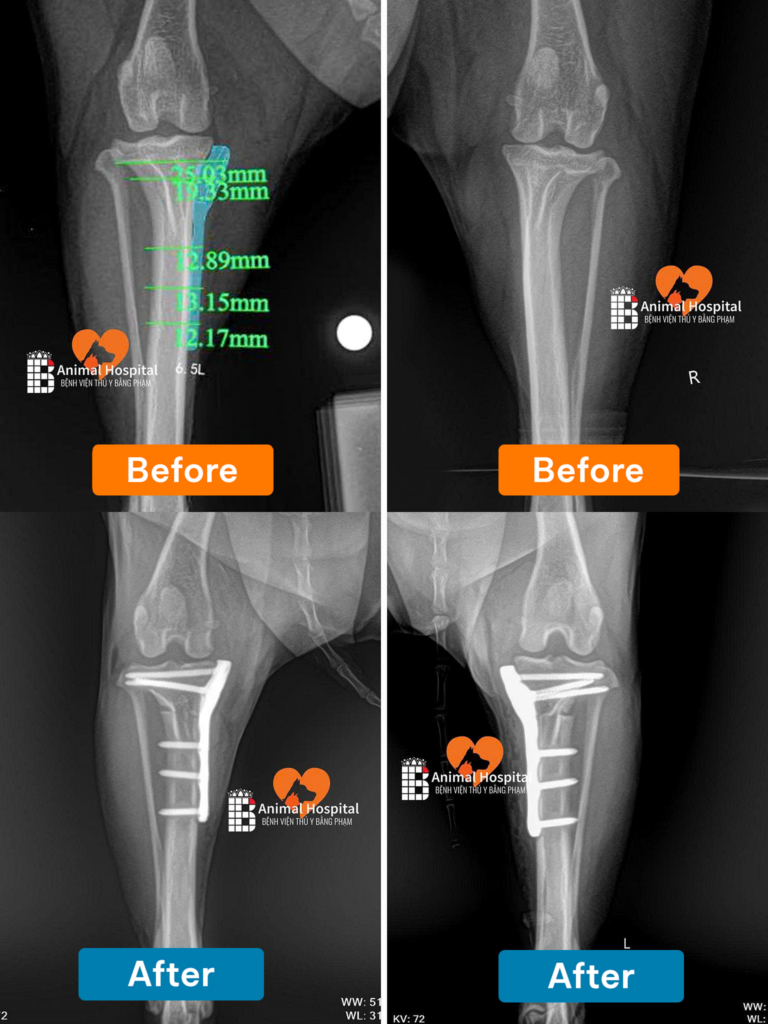

Qua thăm khám lâm sàng (Nghiệm pháp ngăn kéo trượt) và hình ảnh X-quang, bác sĩ chẩn đoán xác định: Milu bị đứt dây chằng chéo trước cả hai bên khớp gối. Khớp mất hoàn toàn sự liên kết cốt lõi, khiến mâm chày trượt tự do về phía trước, triệt tiêu động năng di chuyển và gây đau đớn dữ dội.

Với tình trạng đứt dây chằng song phương, phương pháp mổ thay dây chằng nhân tạo thông thường sẽ không mang lại hiệu quả bền vững. Giám đốc chuyên môn đã quyết định thực hiện phẫu thuật TPLO cho chó (Cắt mâm chày san bằng động lực học).

Khác với các kỹ thuật cũ, TPLO là can thiệp tái cấu trúc sinh cơ học của xương:

• Bác sĩ thực hiện đường cắt cong (Radial cut) trên xương chày, sau đó xoay mâm chày để thay đổi góc độ.

• Khi góc mâm chày được san phẳng, lực đẩy trượt về phía trước sẽ bị triệt tiêu hoàn toàn. Khớp gối đạt được trạng thái ổn định cơ học mà không cần đến sự tồn tại của dây chằng chéo.

• Cấu trúc xương mới được cố định ngàm chặt bằng hệ thống nẹp vít Titanium chuyên dụng thuộc tiêu chuẩn BlueSAO.